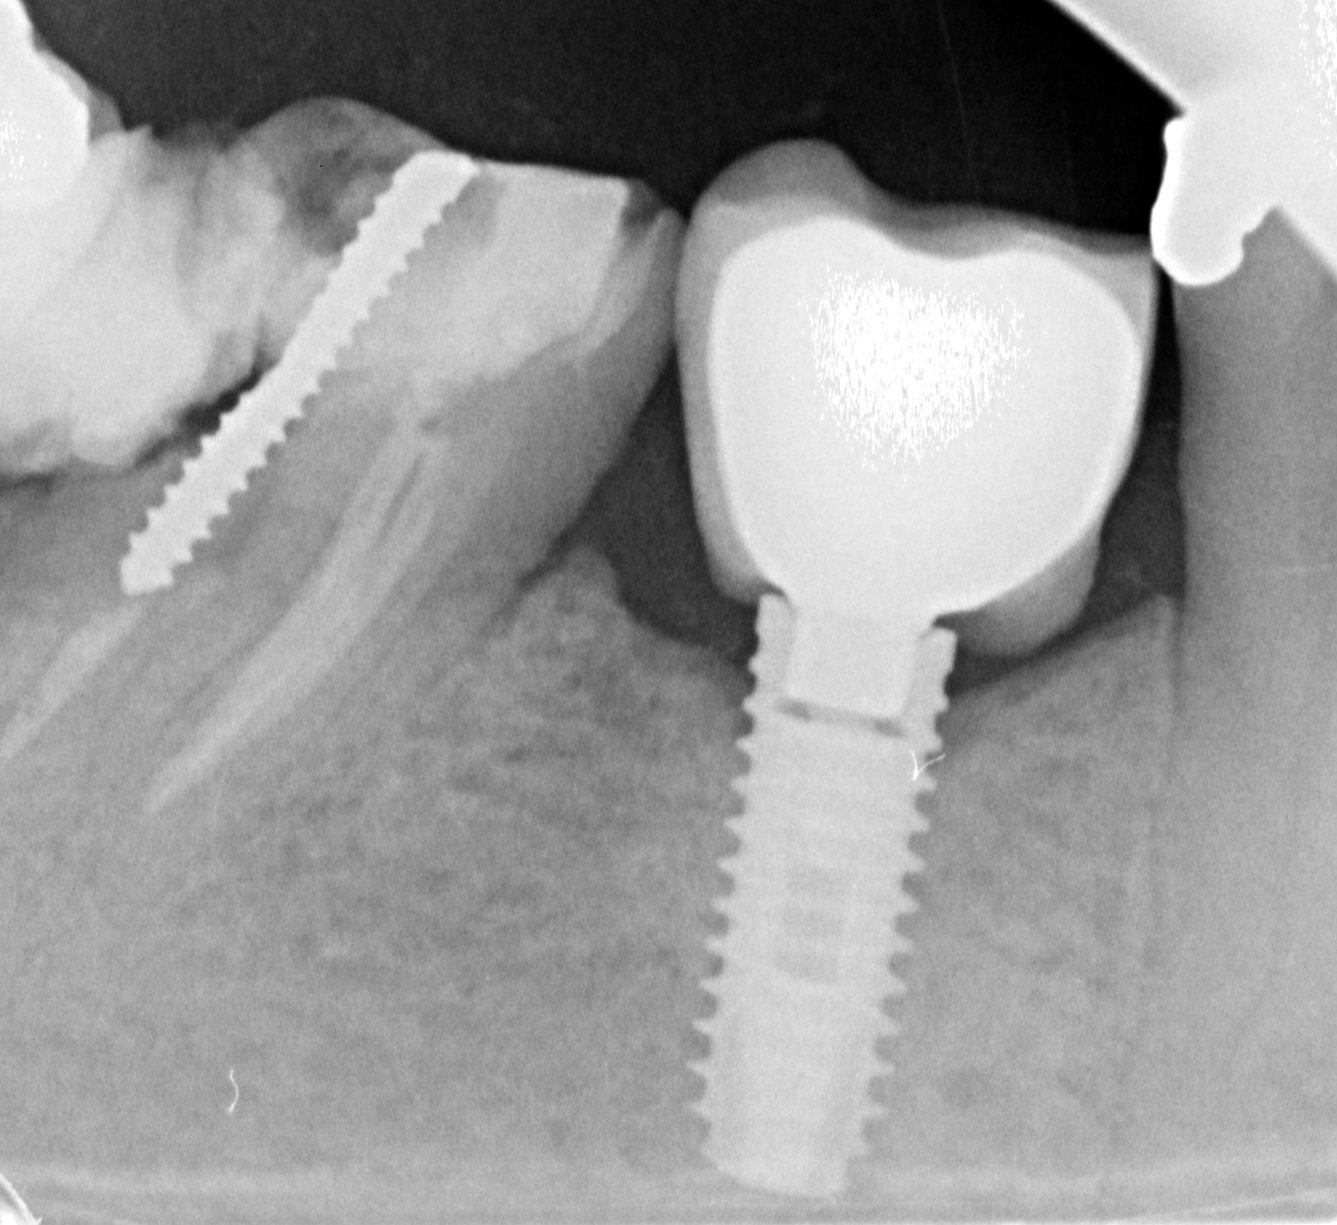

I don't know the type of these 2 implants placed in the mandibular left posterior area Implants have been placed 6 months ago in Egypt